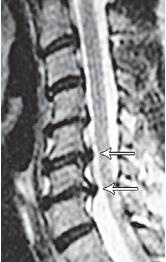

На рентгенограмме № 6 поясничного отдела позвоночника выраженный остеофитоз, спондилёз третьей степени, что также хорошо видно на МРТ № 39 поясничного отдела позвоночника МРТ № 40 ![]() МРТ № 41

На МРТ № 40 наблюдается типичный пример развития стеноза второго типа в шейном отделе позвоночника. И аналогичная картина, только, в поясничном отделе позвоночника, отображена на МРТ № 41 Стеноз Стеноз позвоночного канала встречается довольно часто, во всяком случае в моей практике. В данной книге я уже упоминал о том, что стеноз спинномозгового канала (то есть его сужение) может вызывать серьёзные осложнения при течении таких заболеваний, как например, грыжи межпозвонкового диска. Для лучшего понимания происходящих процессов давайте в общих чертах рассмотрим, что такое стеноз и чем он опасен. Итак, стеноз — это врождённое или приобретённое аномальное сужение просвета какого-либо полого органа (пищевода, кишечника, кровеносного сосуда и др.) или отверстия между полостями (например, при пороках сердца). Стеноз позвоночного канала характеризуется его патологическим сужением. Исходя из анатомо-физиологических особенностей позвоночного канала, который является вместилищем и в тоже время охранным футляром для спинного мозга, даже незначительное его сужение может оказаться фатальным для спинного мозга. К примеру, при развитии абсолютного стеноза позвоночника спинной мозг может быть компримирован (сжат) вместе с артериями. В свою очередь это неизбежно ведёт к развитию ишемии (от греч. ischo — «задерживаю, останавливаю» и haima — «кровь»; уменьшение кровоснабжения участка тела, органа или ткани вследствие ослабления или прекращения притока к нему артериальной крови) тех участков спинного мозга, где блокировано кровоснабжение сдавленными сосудами. Ещё в конце XIX века, а точнее в 1880 году, в своей работе М. Литтен отметил, что спинной мозг более чувствителен к ишемическим повреждениям и недостатку кислорода, чем другие ткани организма. А вот отечественному невропатологу, ученику В. М. Бехтерева и одному из первых нейрохирургов, Л. М. Пуссепу в 1902 году удалось в эксперименте на животных показать, что даже непродолжительная ишемия спинного мозга влечёт за собой некроз (отмирание) нервных клеток передних рогов спинного мозга. Если добавить к этому ещё и неизбежное нарушение ликвородинамики и развития (вследствие сдавления оболочек спинного мозга) эпидурита и арахноидита, то возникновение болевых, корешковых и сосудистых синдромов (в виде миелоишемии, радикулоишемии или миелорадикулоишемии) становятся вполне объяснимыми и понятными. Исходя из классификации, предложенной доктором I. Stephen, которой пользуется большинство авторов в своих работах, стеноз позвоночного канала позвоночника, как я уже упоминал, бывает двух типов. Тип первый — врождённый, или как его ещё называют идиопатический, то есть беспричинный (неизвестного, неясного происхождения). Второй тип — приобретённый, возникший вследствие дегенеративно-дистрофических процессов в позвоночнике, посттравматический или обусловленный другими причинами, которые привели к стенозированию (сужению) позвоночного канала. Например, грыжа межпозвонкового диска даже центральной локализации, имеющая размер всего 6 мм в дорсальном направлении в поясничном отделе позвоночника с сагиттальным размером спинномозгового канала в 15 мм приводит к формированию абсолютного стеноза второго типа (приобретённого) и может вызвать серьёзные осложнения. А при стенозе первого типа (врождённого, см. МРТ № 43), к примеру с сагиттальным размером спинномозгового канала в поясничном отделе 12 мм, даже трёхмиллиметровая протрузия межпозвонкового диска может привести к развитию слабости в ногах, мышечной атрофии или, как описывал данные состояния Dejerine ещё в 1911 г., «перемежающейся хромоте спинальной природы». |